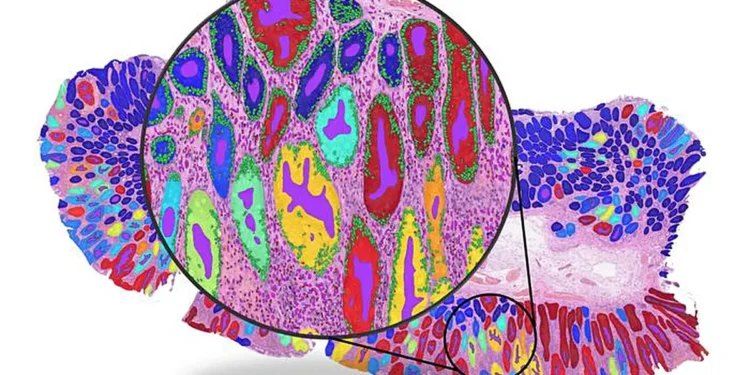

Pour parvenir à cette conclusion, les chercheurs ont analysé plus de 8 000 échantillons de patients à travers quatre types de cancer majeurs — sein, colorectal, poumon et endomètre — et ont comparé les performances des principales approches d’apprentissage automatique. Bien que les modèles aient souvent obtenu une grande précision globale, l’équipe a constaté que cela provenait fréquemment de « raccourcis » statistiques.